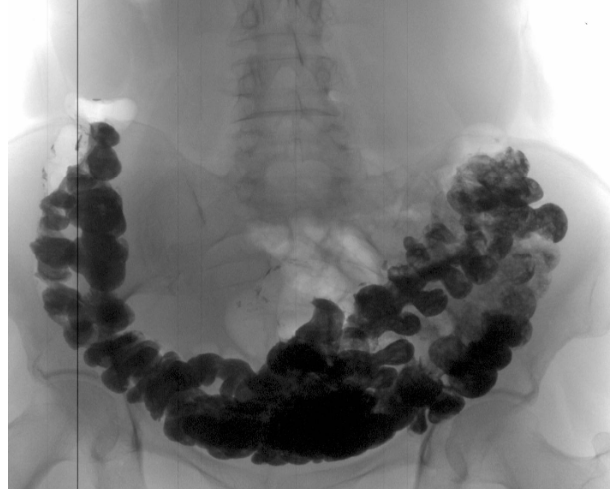

Mire las fotografías de los órganos de personas que inicialmente tenían mal aliento, estreñimiento y acidez de estómago, y terminaron recibiendo el informe de un patólogo.

“Cáncer de colon en una mujer con estreñimiento frecuente

"Ecografía de cálculos fecales en el colon"

"Etapas del cáncer de recto que se desarrollan en 1 o 2 años"

Todas estas personas no hacían nada o usaban productos que les vendían en la farmacia. Pero puedes ver el resultado por ti mismo.